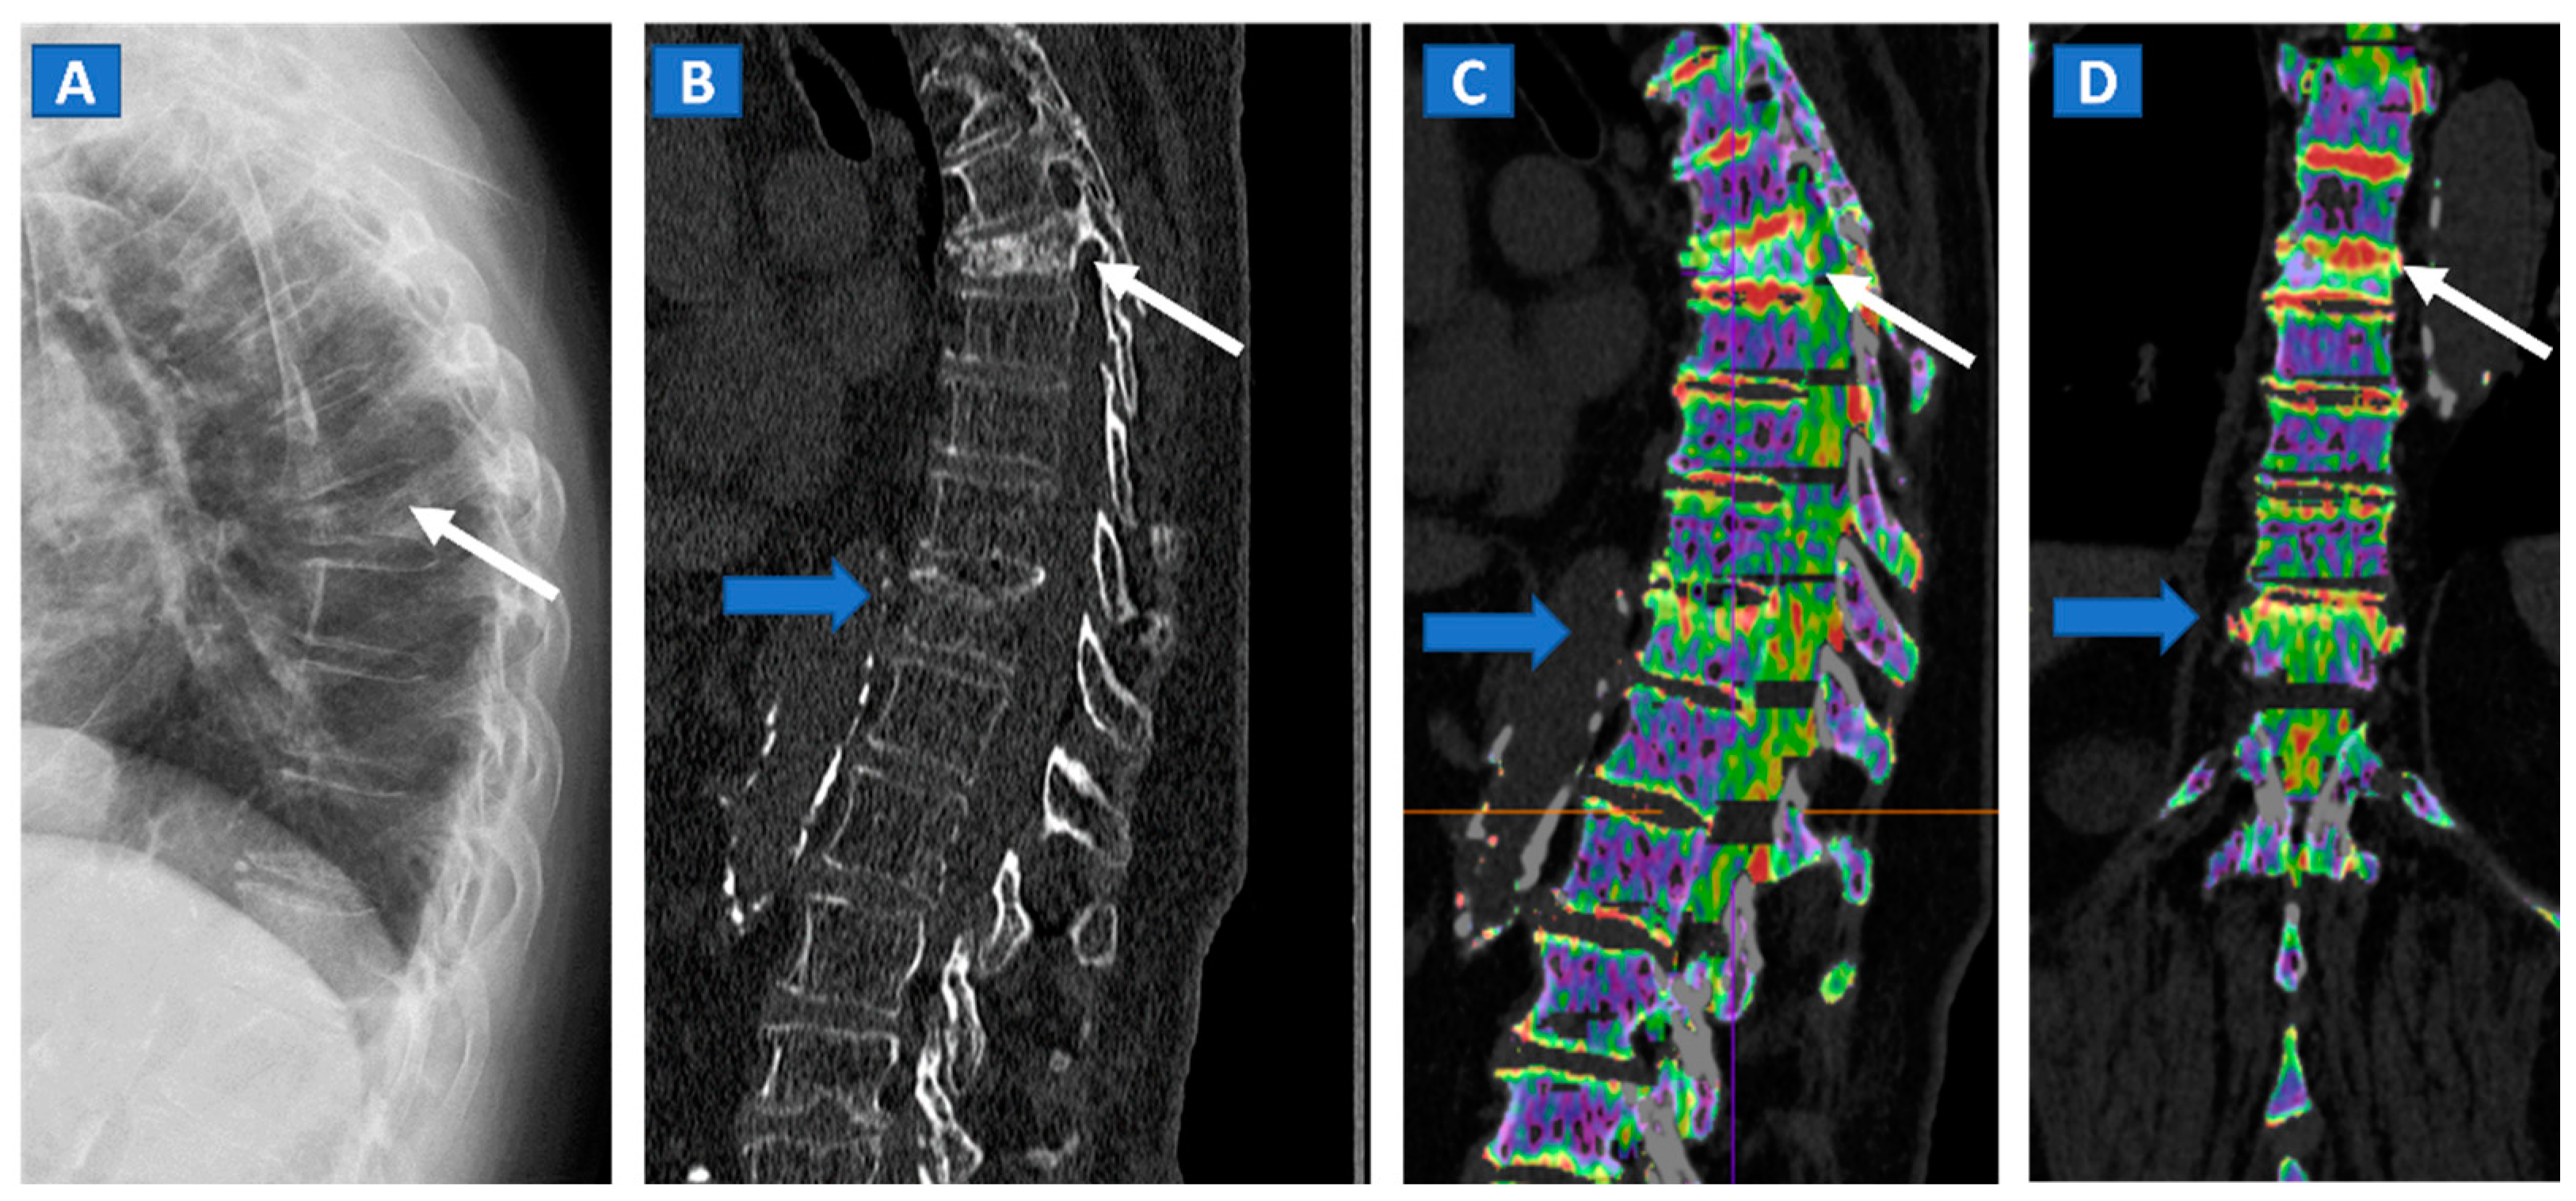

5. Vertebral Compression Fractures